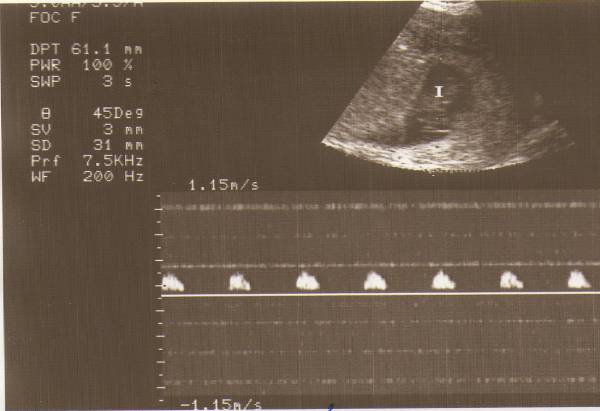

Szóval Kistöki 5,2 mm és erős szívhangja van. Csodálatos érzés volt hallani. Egyszerűen leírhatatlan. Kár, hogy párom nem volt benn, de a hüvelyi uh miatt zavarban lettünk volna egy kicsit szerintem.